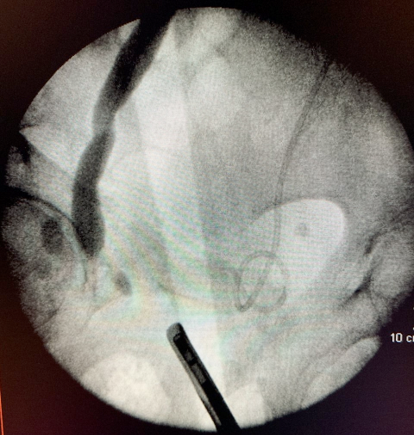

- Nefrostomia direita com punção guida por USG

- Duplo J anterógrado Esquerda

- Troca do duplo J à esquerda e passagem anterógrada à direita